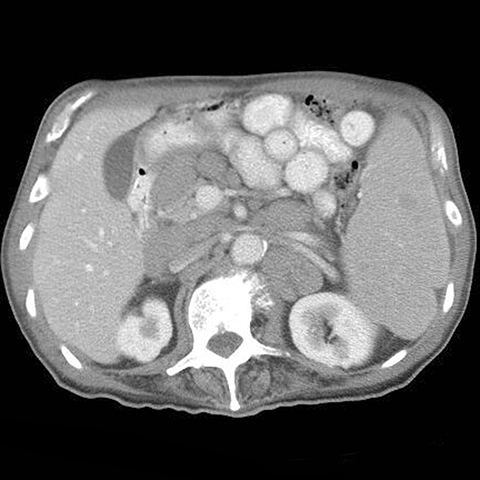

26-year old presents with night sweats and fever. [2 of 2]